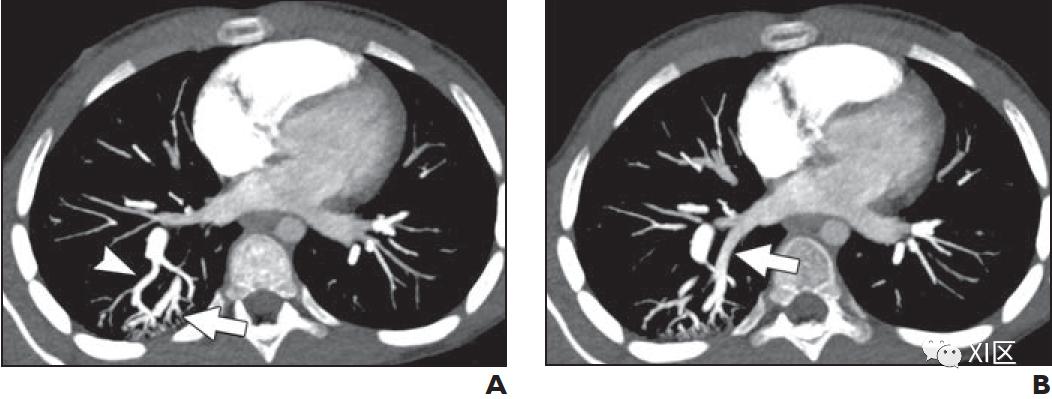

虽然血液动力学不稳定的大咯血患者可能需要通过支气管镜或手术立即治疗,但在稳定的患者中,影像学通常用于确定出血的部位和潜在原因。CTA在63–100%的病例中被反复验证可以定位出血部位。很少在气道中检测到渗出的造影剂。然而,活动性出血的位置可以通过支气管内的液体密度物质或代表肺泡内出血的毛玻璃实变来确定。CTA还可以识别其他潜在的肺实质异常、感染或肿块。也许最重要的是,CTA可以识别异常的肺血管系统,并为计划外科干预或经皮导管栓塞提供路线图(图2)。理想情况下是进行真正的系统动脉期成像,因为支气管动脉来自降主动脉。最大强度投影(MIP)图像增强了支气管动脉和异常血管结构的清晰度。薄层图像能更好地显示小血管结构。

超过90%的咯血需要栓塞或手术干预。导致肺动脉灌注减少的情况,如血管炎和慢性血栓栓塞症,可以增加支气管动脉对肺部的供血。支气管动脉也是绝大多数CF患者咯血的来源。虽然支气管动脉的解剖结构多变,但最常见的结构是一个或两个支气管动脉从中胸部水平降主动脉发出,供应每个肺。有异常起源的支气管动脉,例如来自内乳动脉、肋间动脉或膈动脉的支气管动脉在传统的主动脉造影术中很容易被忽略。支气管动脉直径与出血风险之间的相关性较差,但通常动脉口径超过2 mm被视为异常。

在肺CTA上,PAVMs表现为增强的囊或扩张的血管团块。诊断需要有供血动脉和引流静脉,多平面MIP图像可提高对其的检测能力(图3)。如果可以的话,双能量扫描可以提供一个虚拟平扫序列,以排除疑似PAVM的钙化结节。

供血动脉的直径应在动静脉交通的近端、实质分支的远端大约2-3厘米测量。动脉直径大于3毫米表明病变可能适合经导管栓塞(图3)。如果PAVM不符合栓塞术的条件,建议随访肺部CTA以监测其生长情况。在儿科人群中,理想的随访间隔并不是很明确,常见的随访间隔为1到10年。Ratjen等人在HHT患儿中发现PAVM的平均年增长率约为10%。